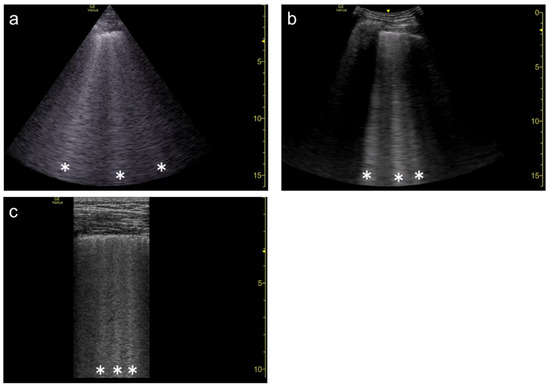

3.2. Focal Point